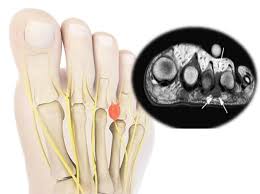

또한 척추관 협착증은 신경이 지나는 척추관이 좁아지며 발생하며, 걸을 때 다리가 저리다 쉬면 괜찮아지는 특징적인 증상이 있어요. 이외에도 좌골신경통, 당뇨병성 신경병증, 발목터널증후군 등 다양한 질환이 발저림 원인으로 작용합니다.